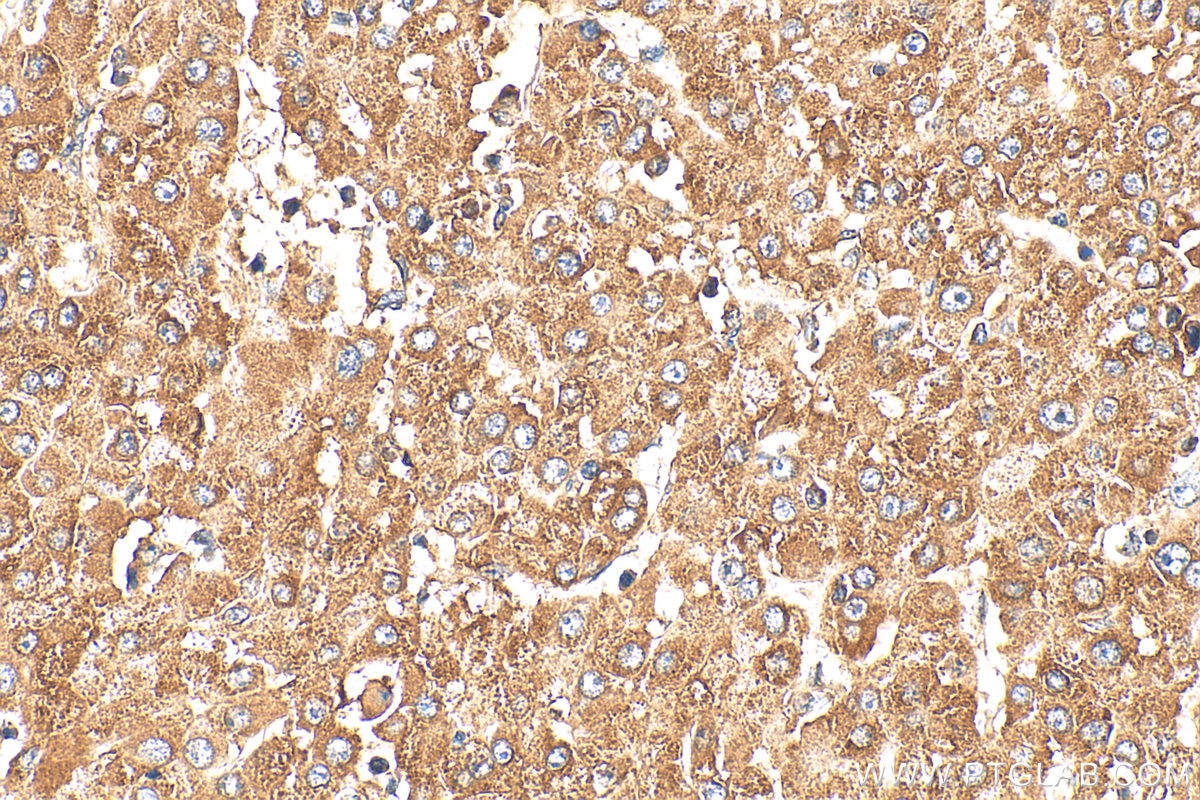

| Positive IHC detected in | human liver cancer tissue Note: suggested antigen retrieval with TE buffer pH 9.0; (*) Alternatively, antigen retrieval may be performed with citrate buffer pH 6.0 |

| Immunohistochemistry (IHC) | IHC : 1:50-1:500 |